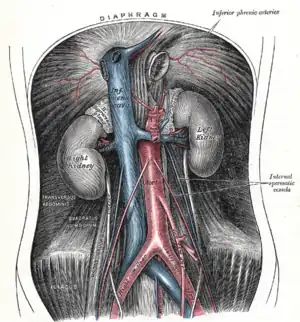

The abdominal aorta and its branches. | |

The abdominal aorta begins at the level of the diaphragm, crossing it via the aortic hiatus, technically behind the diaphragm, at the vertebral level of T12.[1] It travels down the posterior wall of the abdomen, anterior to the vertebral column. It thus follows the curvature of the lumbar vertebrae, that is, convex anteriorly. The peak of this convexity is at the level of the third lumbar vertebra (L3). It runs parallel to the inferior vena cava, which is located just to the right of the abdominal aorta, and becomes smaller in diameter as it gives off branches. This is thought to be due to the large size of its principal branches. At the 11th rib, the diameter is 122mm long and 55mm wide and this is because of the constant pressure.[2] The abdominal aorta is clinically divided into 2 segments:

The abdominal aorta supplies blood to much of the abdominal cavity. It begins at T12 and ends at L4 with its bifurcation into the common iliac arteries[1] and usually has the following branches:

The abdominal aorta lies slightly to the left of the midline of the body. It is covered, anteriorly, by the lesser omentum and stomach, behind which are the branches of the celiac artery and the celiac plexus; below these, by the lienal vein (splenic vein), are the pancreas, the left renal vein, the inferior part of the duodenum, the mesentery, and the aortic plexus.

Posteriorly, it is separated from the lumbar vertebrae and intervertebral fibrocartilages by the anterior longitudinal ligament and left lumbar veins.

On the right side it is in relation above with the azygos vein, cisterna chyli, thoracic duct, and the right crus of the diaphragm—the last separating it from the upper part of the inferior vena cava, and from the right celiac ganglion; the inferior vena cava is in contact with the aorta below.

On the left side are the left crus of the diaphragm, the left celiac ganglion, the ascending part of the duodenum, and some coils of the small intestine.

The abdominal aorta's venous counterpart, the inferior vena cava (IVC), travels parallel to it on its right side.

- Above the level of the umbilicus, the aorta is somewhat posterior to the IVC, sending the right renal artery travelling behind it. The IVC likewise sends its opposite side counterpart, the left renal vein, crossing in front of the aorta.

- Below the level of the umbilicus, the situation is generally reversed, with the aorta sending its right common iliac artery to cross its opposite side counterpart (the left common iliac vein) anteriorly.